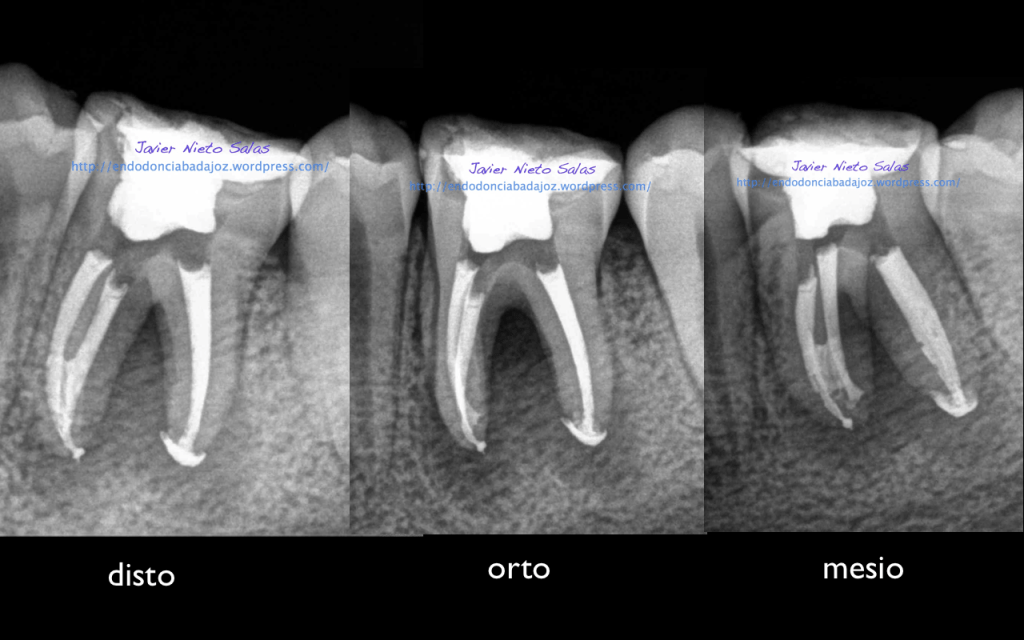

Se trata de un par de molares inferiores con lesiones apicales (Periodontitis apicales crónicas ). Consecuencia de caries profundas en su momento.

Se tratan del caso A y el caso B, por orden de posición, ambos casos se instrumentaron de la misma manera, elegimos Protaper hasta una F2, ambos casos se realizaron en una sesión tras abundante irrigación y finalmente se obturaron con condensación Vertical con la técnica de Ola continua de Buchanan complementando en el backfilling con guatpercha inyectada con la Pistola Obtura II.

Caso B:

También se llamo a revisión a los 10 meses.

Con respecto a tu pregunta sobre las dos últimas Rx, que son la revisión de las anteriores, de una periodontitis apical crónica de un 4.6, si puedes observar en la radiografía distalizada final, existe un istmo entre ambos conductos, y puede ser que exista un conducto lateral, pero como ya sabemos, existe una gran complejidad anatómica del sistema de conductos. El blog de Ronal Ordinola, es fantástico, y puedes ver esas anatomías en las que piensas en que la endodoncia es un verdadero RETO.